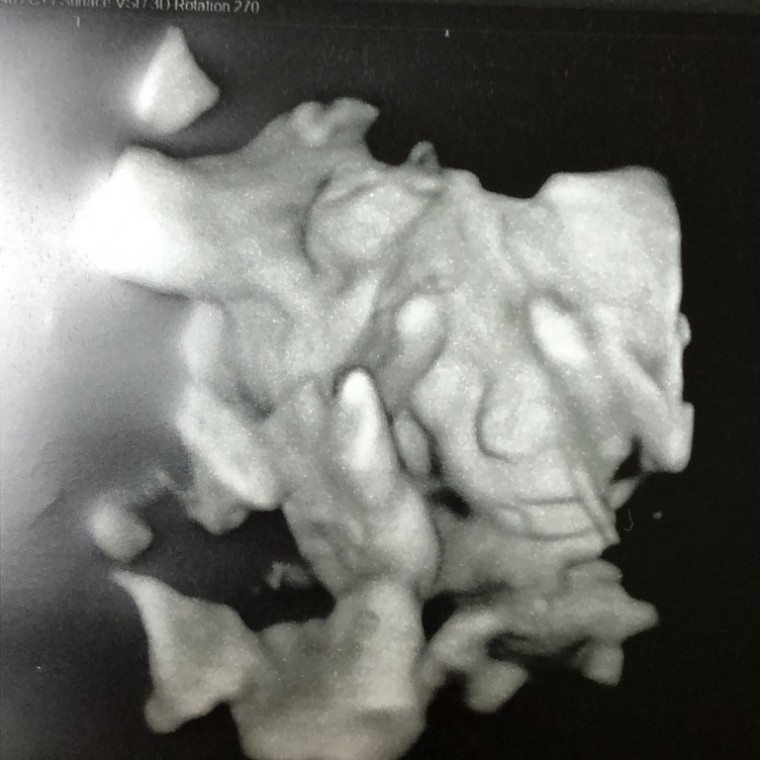

妊娠7ヶ月の超音波写真

妊娠7ヶ月(24週3日)撮影日:2018年9月12日

妊娠7ヶ月(26週3日)撮影日:2018年9月12日

妊娠7ヶ月(25週3日)撮影日:2018年9月18日

妊娠7ヶ月(25週2日)撮影日:2018年2月03日